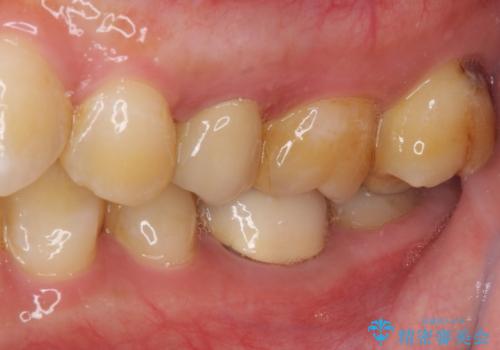

来院されたときには、神経を全て取り除くことになるであろうと思っていらっしゃいましたが、結果としては歯根部分の歯髄を残すことができました。

神経組織を全部または部分的に除去することが分かっていたため、ラバーダムなどの環境を整え、無菌的環境下にて処置を進めて行きました。

虫歯は深くまで進行しており、歯冠部の神経から出血が認められました。神経を部分的に除去したところ出血が治まったので、生体親和性の非常に高いセメントにて充填し、仮封をしました。

後日状態を確認したところ、残された神経に異常は認められませんでした。

欠損歯質は比較的小さかったため、セラミックインレーにて修復治療を行いました。